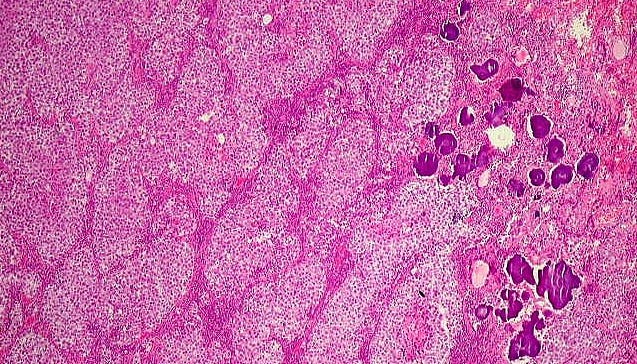

Germinoma, um tipo específico de TCG que ocorre mais frequentemente no cérebro: tumores raros, heterogêneos e difíceis de estudar (imagem: Departamento de Anatomia Patológica/FCM-Unicamp)

“Os tumores de células germinativas podem acontecer tanto em adultos quanto em crianças e adolescentes. No público pediátrico, eles são muito raros, representam cerca de 3% dos tumores. Pela raridade e pela heterogeneidade, são tumores difíceis de estudar”, explica Mariana Tomazini, orientadora do estudo e pesquisadora do CPOM.

Segundo ela, os TCGs podem surgir em diferentes localizações: ovários, testículos, sistema nervoso central e retroperitônio, dentre outros, e ainda apresentam diferentes tipos histológicos, ou seja, variações na aparência celular e no padrão de crescimento. “É como se fosse uma ‘assinatura’ do tumor, um sobrenome. Isso porque dentro do mesmo órgão, podemos ter tumores com características distintas. Esse subtipo, ou tipo histológico, ajuda os médicos a definir o diagnóstico e escolher a melhor estratégia de tratamento”, diz Tomazini.